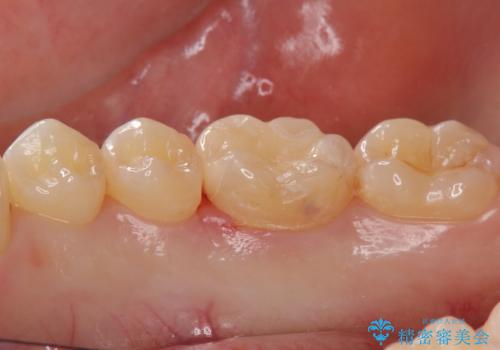

矯正後の虫歯治療 セラミックインレーでの治療

- 矯正後の虫歯治療です。

咬む面と歯と歯の間の虫歯に対してセラミックインレーでの修復処置をしていきます。

- 右下6 セラミックインレー 77,000円費用は治療当時の料金となります

下の奥歯は外から見える場所です。審美的なセラミックでの治療をおすすめします。